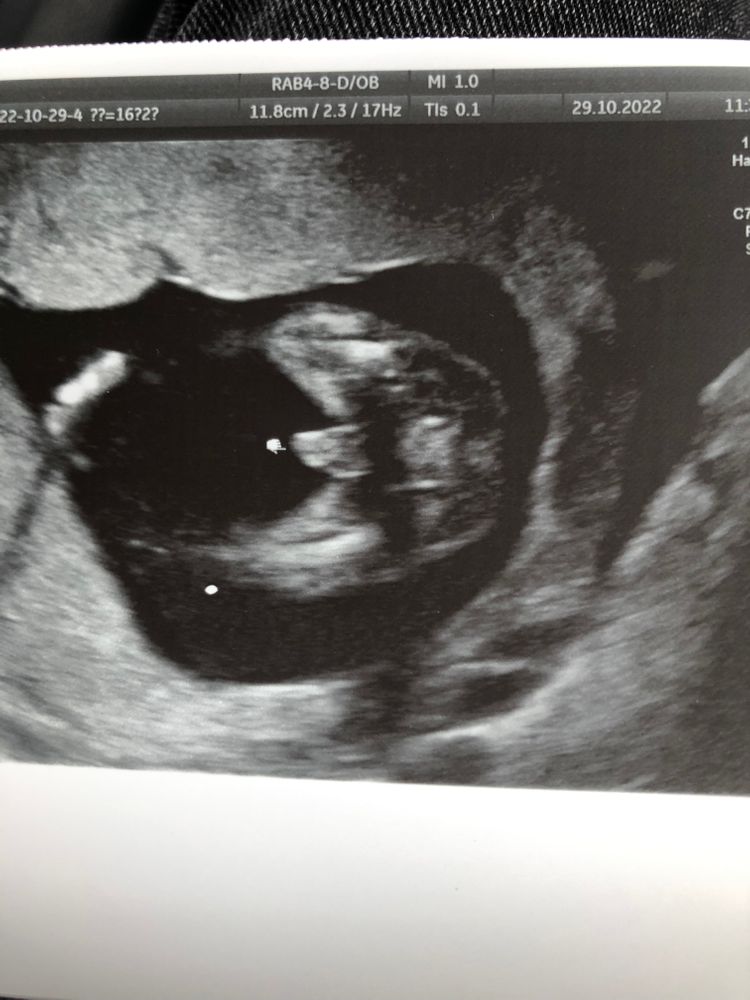

My life my love, чуйка вас не подвела 😁😁

😌😌

У вас точно мальчик))) поздравляю.